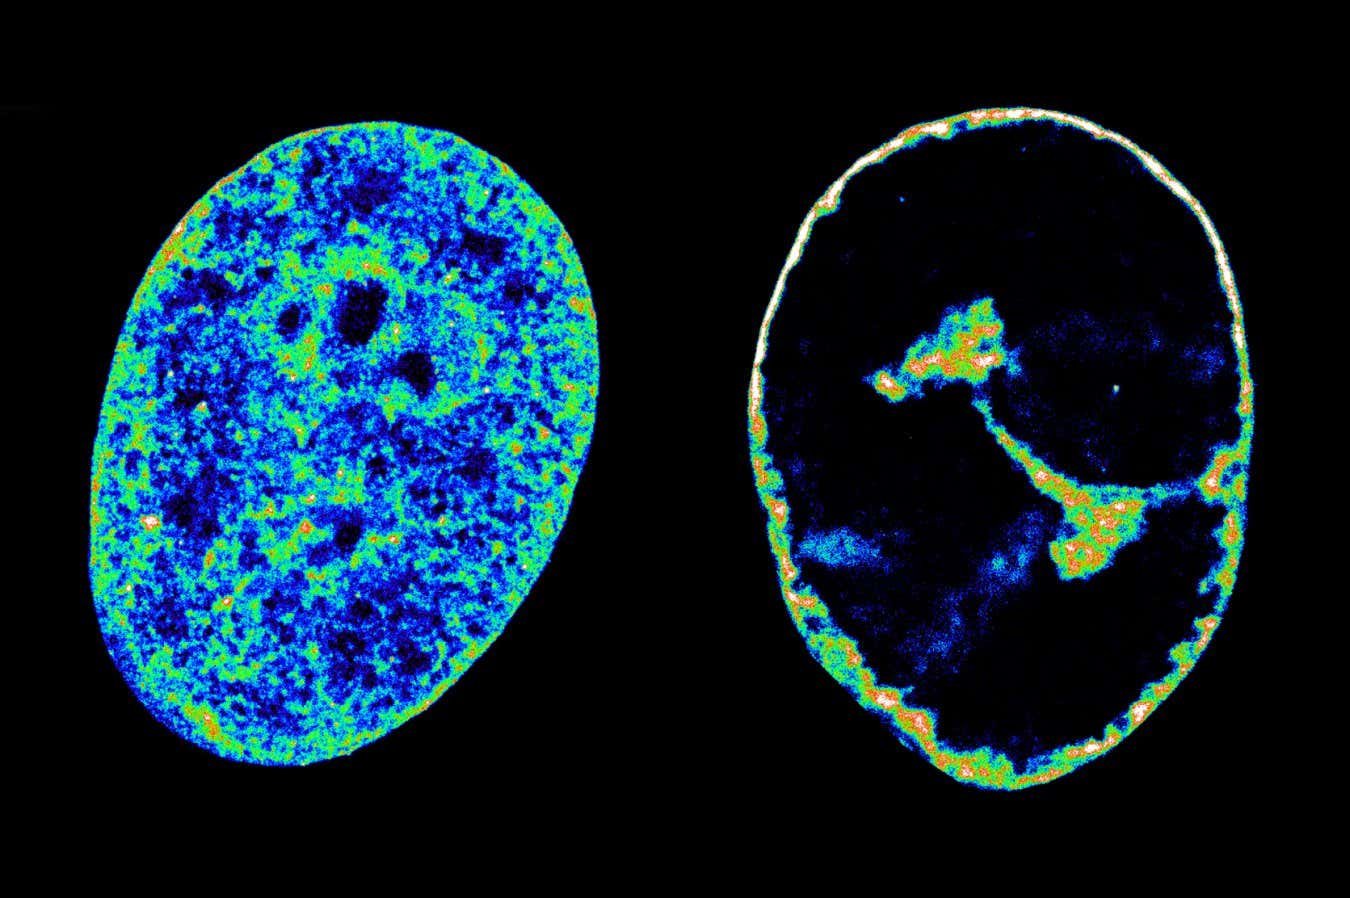

Human DNA in its natural state inside cells (left) compared with its state eight hours after being infected with the cold sore virus (right)

But they also showed that this theft is what seems to cause the host DNA to coil up more tightly, making it shrink to 30 per cent of its pre-infection volume within eight hours of infection.